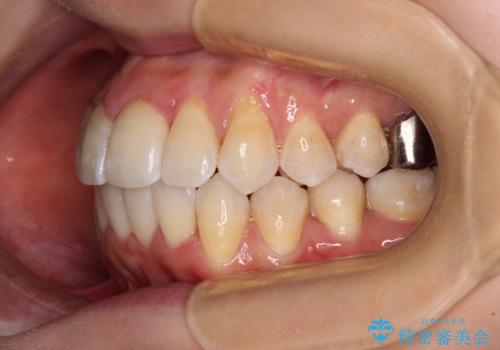

3. 【モニター】急速拡大装置 狭い歯列を拡大してワイヤー装置で短期間治療の治療後